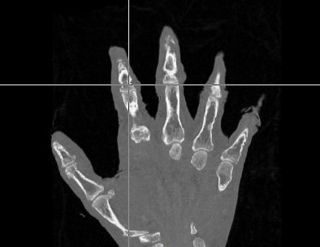

Integrate additional ITK transform types into the neural network using the general ITK transform I/O mechanism. Evaluate the changes to segment the phalanx bones bones of the hand.

- The first was that we have integrated a rigid body initialization for a Thirion Demons registration for atlas <-> subject registration. The above modification was used to warp the atlas to the subject as shown in the figures.